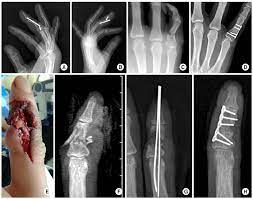

A 28 Year Old Man Sustained Middle Phalanx Fracture Of Right Index Download Scientific Diagram

A 52 Year Old Woman Sustained Middle Phalanx Open Fracture Of Left Download Scientific Diagram